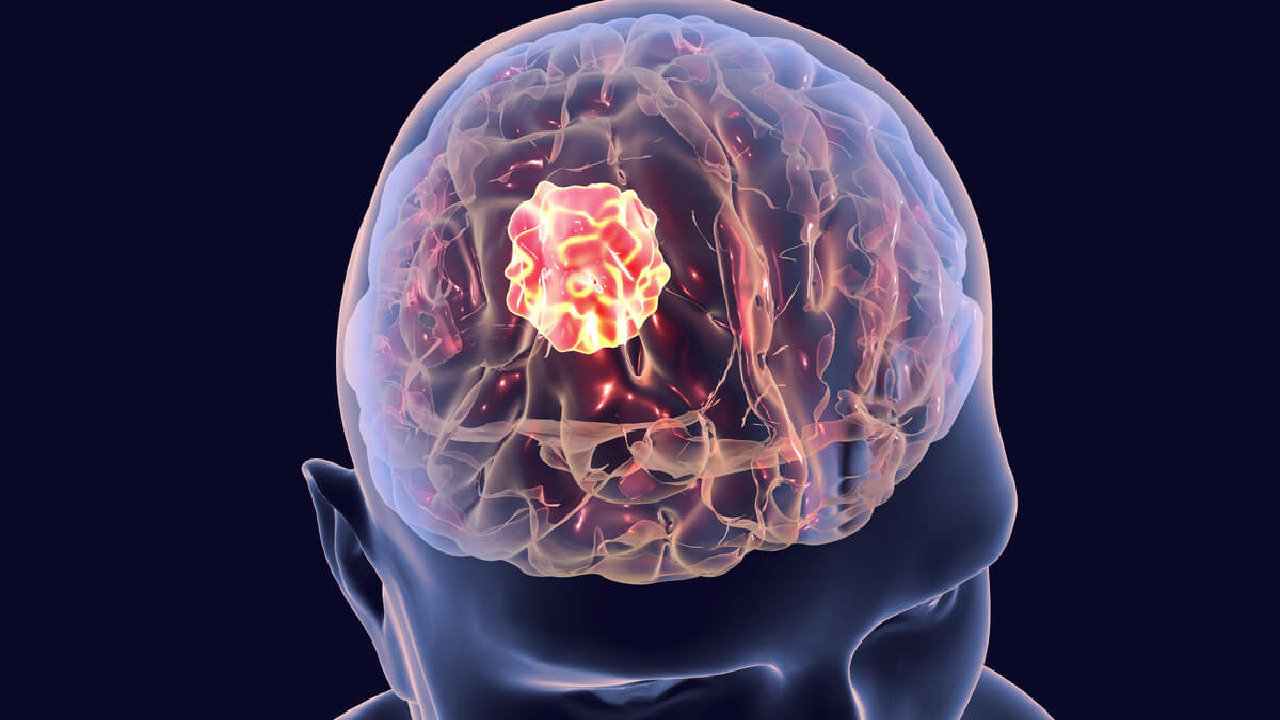

5 أشياء تسبب الإصابة بـ ورم المخ

منذ 3 سنة

0

2412